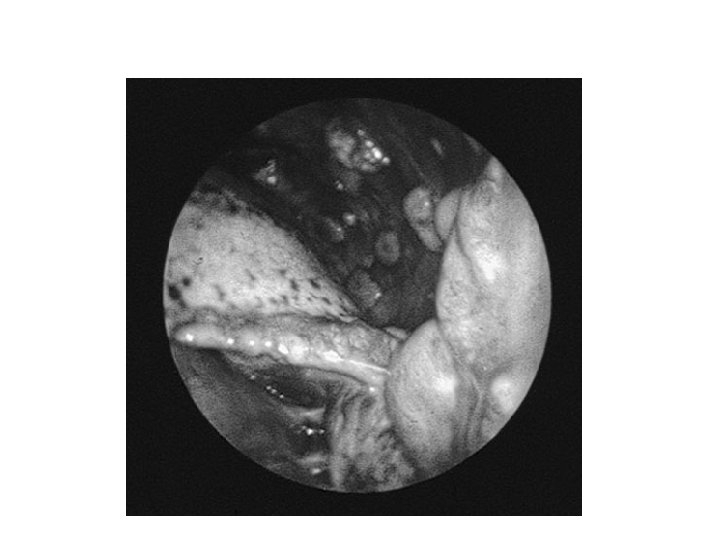

Que faites-vous? • Ponction pleurale exploratrice : – Biochimie (ac hyaluronique) – Cytologie/ana-path • Biopsie pleurale? • Thoracoscopie – Diagnostic – « Traitement »

Cas clinique

Quel diagnostic suspectez vous? Mésothéliome

Le mésothéliome • Exposition à l’amiante dans 80% des cas, parfois très ancienne ou indirecte • Diagnostic difficile : biopsies sous thoracoscopie • Parfois asbestose connue avant • Traitement curatif rare et lourd / Palliatif – – Symphyse pleurale Chimiothérapie Radiothérapie sur le trajet des drains / antalgique Évolution loco-régionale

Poumon nécropsique après mésothéliome